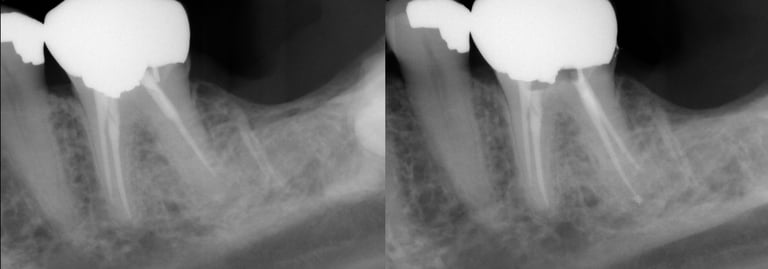

Gallery 2: Retreatment Cases

Retreatment Root Canal Cases with preoperative and postoperative radiographs.

#30 ReTx (original RCT had missed canal)

#19 ReTx (original had missed canal)